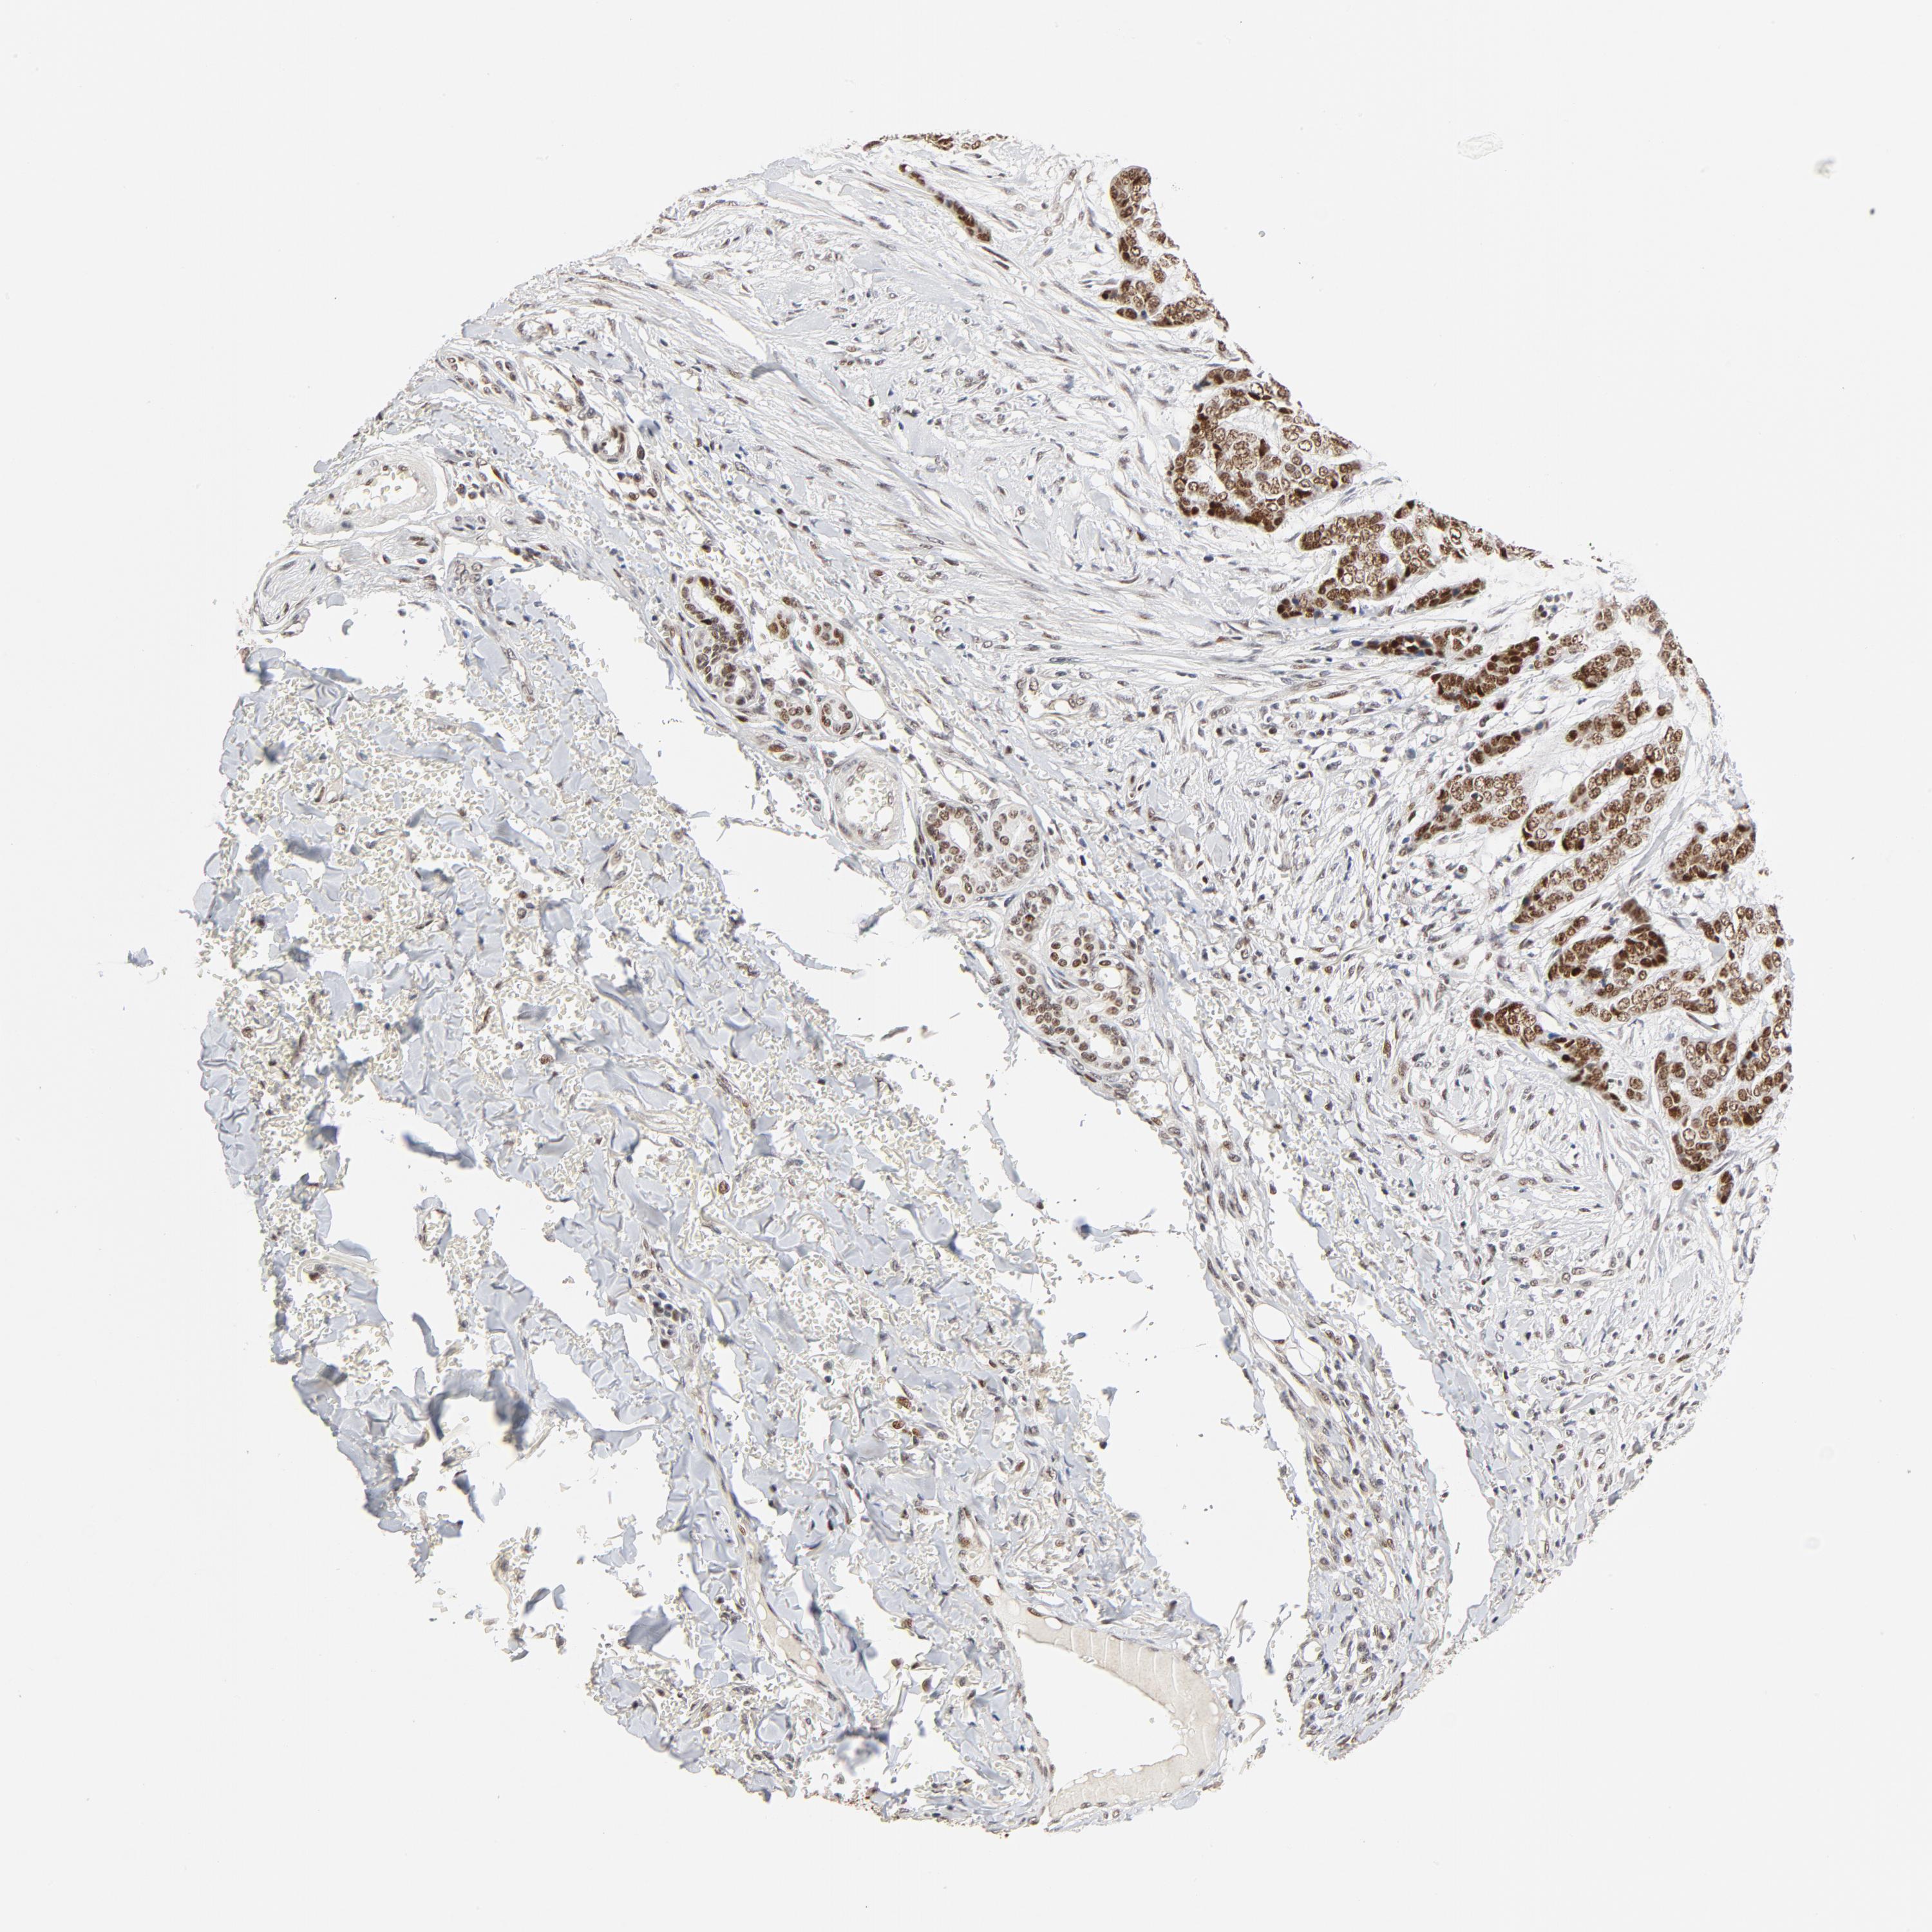

SKIN CANCER - Protein expressioni

A mouse-over function shows sample information and annotation data. Click on an image to view it in a full screen mode. Samples can be filtered based on level of antibody staining by selecting one or several of the following categories: high, medium, low and not detected. The assay and annotation is described here.

Antibody stainingi

Antibody staining in the annotated cell types in the current human tissue is reported as not detected, low, medium, or high, based on conventional immunohistochemistry profiling in selected tissues. This score is based on the combination of the staining intensity and fraction of stained cells.

Each image is clickable and will lead to virtual microscopy that enables deeper exploration of all samples and also displays staining intensity scores, fraction scores and subcellular localization as well as patient and tissue information for each sample.

Antibody HPA026638

Antibody CAB004595

Basal cell carcinoma

Squamous cell carcinoma, NOS

Squamous cell carcinoma, metastatic, NOS